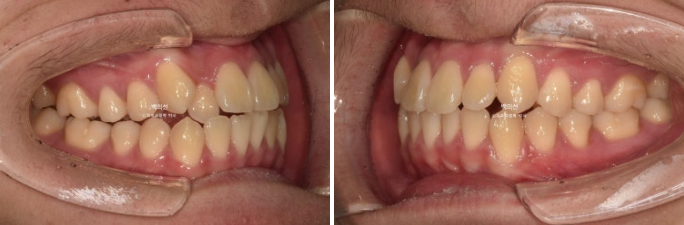

덧니와 반대교합은 해소가 되었습니다.

교합은 좋고 양쪽 다 1급 교합관계를 보입니다.

24.12

24.04~25.07